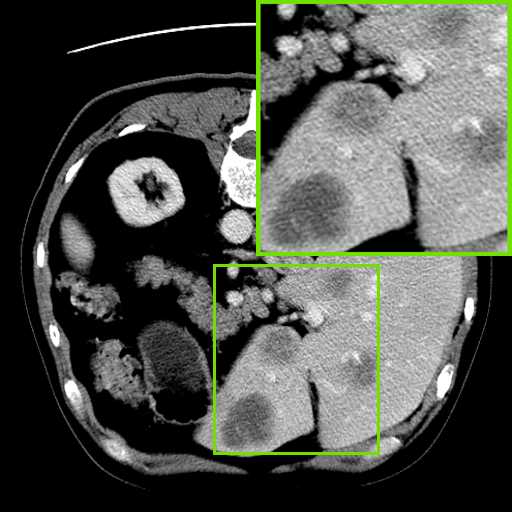

Figure 4: Qualitative analysis visualization of Feature Enhanced Decoder (FED) on four datasets.

IV-C2 Qualitative analysis of Feature Enhanced Decoder

We also perform qualitative analyses on several cases, as illustrated in Fig. 4. The visualizations indicate that removing the original image features leads to a significant inaccuracy in the size of the segmented regions across the four datasets. This outcome underscores the importance of the original image features in accurately capturing the size of the target region. This aligns with our intuition that incorporating the original image information enhances the spatial features, resulting in more precise segmentation in both size and shape.